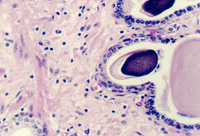

The Prostate epithelium looks cuboidal or pseudostratified low columnar in spots. Inside the glandular lumena you may see laminated bodies known as concretions. These are evident in the following photograph and help identify the organ as the prostate.

In the connective tissue there are bundles of smooth muscle which stand out

because of their homogeneous cytoplasm. Find smooth muscle in the above photograph

or the one below. What components of semen are contributed by the prostate?